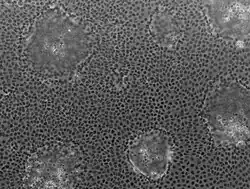

Caco-2 (from Cancer coli, "colon cancer") is an immortalized cell line of human colorectal adenocarcinoma cells. It is primarily used as a model of the intestinal epithelial barrier.[1] In culture, Caco-2 cells spontaneously differentiate into a heterogeneous mixture of intestinal epithelial cells.[1] It was developed in 1977 by Jorgen Fogh at the Sloan-Kettering Institute for Cancer Research.[2]

Microscopically, Caco-2 cell cultures show obvious heterogeneity likely reflecting the complex mixture of cells found in the epithelial lining of the large and small intestine i.e. enterocytes, enteroendocrine cells, goblet cells, transit amplifying cells, paneth cells and intestinal stem cells.[5] Over time, the characteristics of the cells used in different laboratories have diverged, introducing inter-laboratory variation.[6] Despite such heterogeneity, Caco-2 cells are used in cell invasion studies, viral transfection research, and lipid transport.[7]